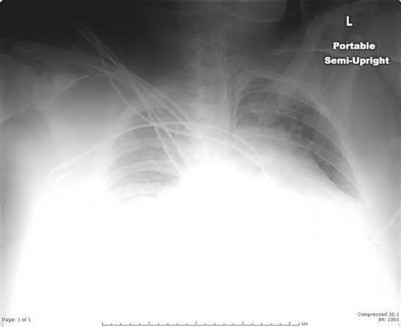

A 33-year-old secretary presents three months after a motor vehicle collision with a mild asymmetry to her sternal area and difficulty swallowing. She denies any complaints of respiratory distress or upper extremity paresthesias. Her upper extremity neurovascular exam shows no deficits. A 3-D computed tomography image is shown in Figure A. What is the most appropriate treatment for this patient?

The clinical presentation is consistent with a chronic sternoclavicular dislocation, which is defined as being greater than 3 weeks old. The 3D CT image shows posterior displacement of the medial clavicle relative to the sternum. Chronic anterior dislocations are recommended to be treated conservatively, especially if not symptomatic, but as this is a posterior dislocations, current recommendations are to treat them with reduction in order to avoid delayed issues with the medial clavicle interacting with the mediastinal structures.

The review article by Wirth and Rockwood notes the following complications with posterior dislocation: respiratory distress, venous congestion or arterial insufficiency, brachial plexus compression, and myocardial conduction abnormalities. They recommend reconstruction of the costoclavicular ligaments with resection of the medial claviclar head as needed for unstable or symptomatic injuries.